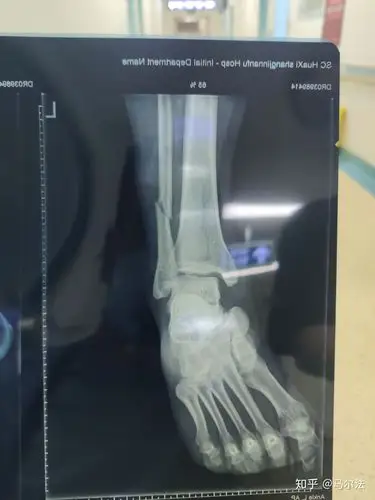

打球崴脚了 麻烦看一下x片

泡 冰敷 没有肿 但是走路完全无法使劲儿 间隔8小时 还是去医院拍片了